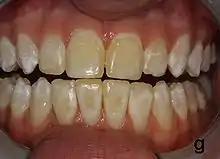

| Mild fluorosis: in its usual mildest form, fluorosis appears as opaque white patches on the enamel | |

It appears as a range of visual changes in enamel[4] causing degrees of intrinsic tooth discoloration, and, in some cases, physical damage to the teeth. The severity of the condition is dependent on the dose, duration, and age of the individual during the exposure.[1] The "very mild" (and most common) form of fluorosis, is characterized by small, opaque, "paper white" areas scattered irregularly over the tooth, covering less than 25% of the tooth surface. In the "mild" form of the disease, these mottled patches can involve up to half of the surface area of the teeth. When fluorosis is moderate, all of the surfaces of the teeth are mottled and teeth may be ground down and brown stains frequently "disfigure" the teeth. Severe fluorosis is characterized by brown discoloration and discrete or confluent pitting; brown stains are widespread and teeth often present a corroded-looking appearance.[1]